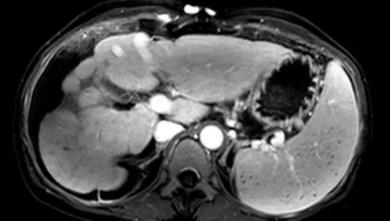

布查氏综合症主要的表现就是肝,脾异常增大,并且造成腹部积水,肚子肿大。

体内肝部的静脉堵塞之后,血液无法正常流通,肯定不能再回流,

那就只能是慢慢往外渗出,逐渐的形成腹水。

现在吴远碧的肚子里全是腹水,首要目的是得把她体内的积水给抽出去,

不然一旦压迫到心脏,很有可能给她带来生命危险。

在手术开始之后,医生从吴碧远的肚子里足足抽出来60多斤的腹水,